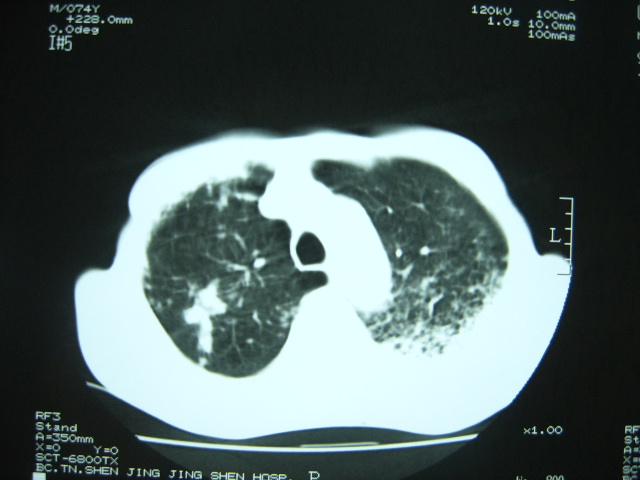

男74岁,咳嗽,寒战,低烧。有糖尿病史。

两肺结核,空洞形成,左下肺肺段隔离症待排

考虑:1、左下肺脓肿;

2、双肺结核。

考虑:糖尿病合并:1、左下肺炎继发肺脓肿;

考虑:1、左下肺脓肿;不排除霉菌感染

1、左下肺肺脓肿,合并霉菌球形成?.2、双肺陈旧性病灶.3、右上肺病灶警惕瘢痕癌,建议定期复查.

两肺结核,左下肺大片实变,内见空洞性病变,壁不规则,结合糖尿病史,考虑:结核性?霉菌性?建议结合实验室检查或治疗后复查。